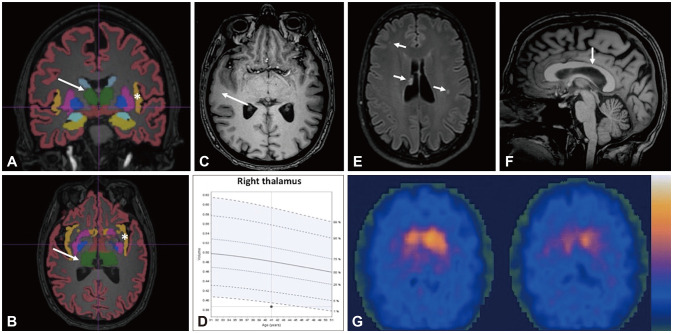

Early-Onset Parkinson's Disease in a Patient With a De Novo Frameshift Variant of the ANKRD11 Gene and KBG Syndrome.

ANKRD11基因从头移码变异患者的早发性帕金森病和KBG综合征